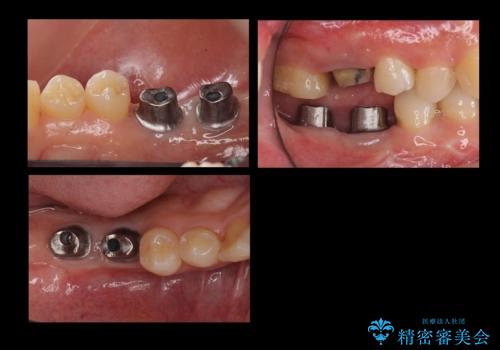

右上に部分矯正を行い、クリアランスを確保した後、右下にイプラントを2本埋入しています。

- およそ150万円 部分矯正30万円、インプラント治療37万円×2本、右上7emaxインレー、右上6 専門医による再根管治療およびジルコニアクラウン26万円費用は治療当時の料金となります

上の歯が伸びだしてきていたため、部分矯正を行い歯を移動させてから、向かい合わせの歯にインプラント治療を行っています。